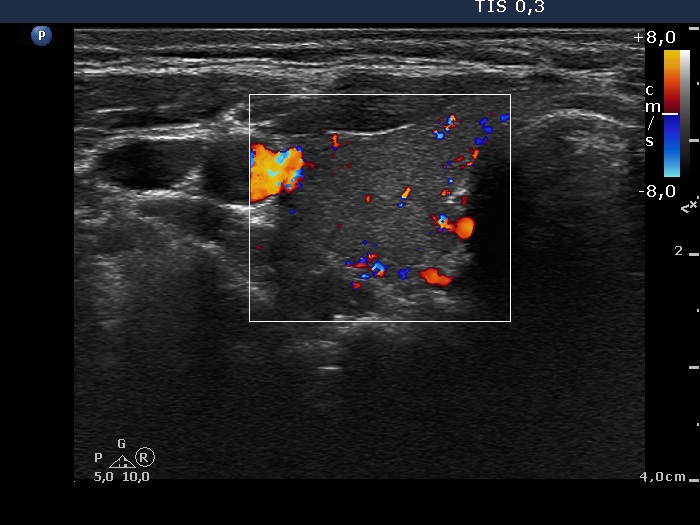

Third examination 24 months after initial investigation (3rd row of images)

Clinical data: The thyrostatic therapy was stopped 13 months ago. The patient had no complaints.

Palpation: unchanged.

Results of blood tests: euthyroidism (TSH 0.52 mIU/L, FT4 14.6 pM/L).

Ultrasonography: The size of the thyroid decreased further. The echo structure and the vascularization became normal.

Suggestion: to check the thyroid function every year, in the event of complaints or pregnancy at once.

Comment. This case demonstrates typical course of non-relapsing Graves disease. The change in hormone levels and in the ultrasound pattern are parallel.